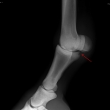

Čip ve spěnkovém kloubu na pánevní končetině

Ankylóza spěnkovýho kloubu

rentgenologické vyšetření